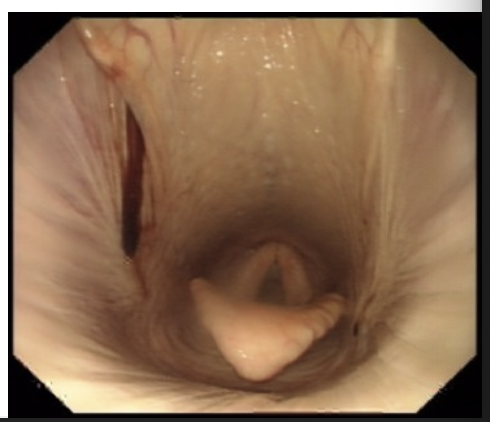

What can you see in this image?

Epiglottis = leaf shaped structure

Arytenoid cartilages behind

Haemorrhage from guttural pouch can be seen on right side of image